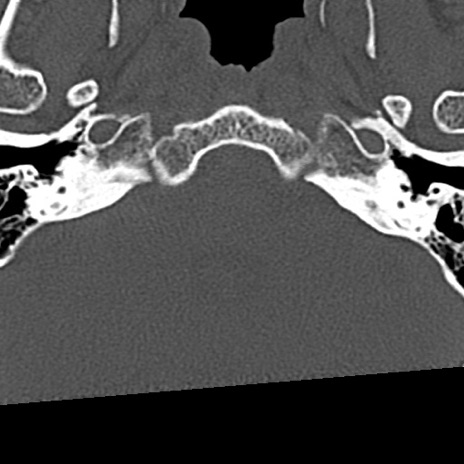

頚椎CT

冠状断像